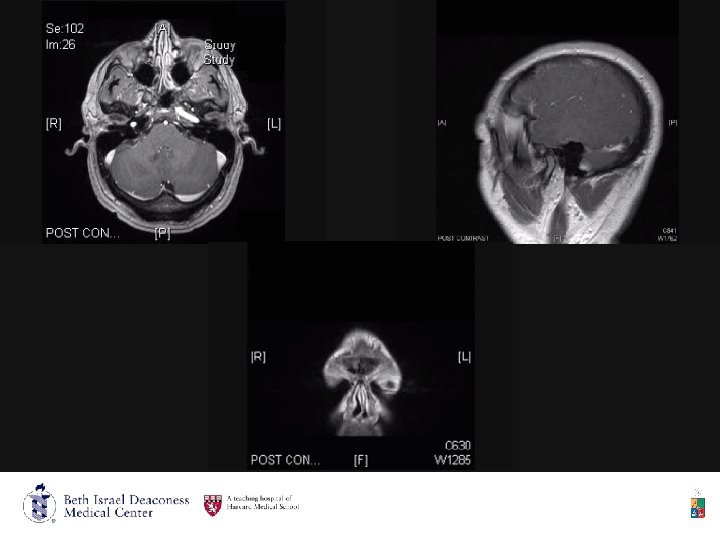

• 6/23/09 MRI Head and Orbits w & w/o contrast: • 2. 8 x 2. 7 x 2. 1 cm lesion within the left retro-orbital space and middle cranial fossa, adjacent soft tissues, laterally and into infra-temporal fossa, and pre-septal soft tissues, with osseous destruction involving sphenoid wing and intra-orbital extension causing mass effect upon the rectus muscles, optic nerve and globe. There is no intra-conal or intra-axial cerebral extension.

• Impression: • This most likely represents chronic aggressive infection , fungal or indolent bacterial, with or without foreign body reaction. • The differential includes: • Langerhans cell histiocytosis • Round cell tumor • Rhabdomyosarcoma

• Skull LCH is characteristically isointense to gray matter on T 1 weighted and enhances homogeneously on CT and MRI after contrast administration. (Binning, Mandy J (MJ); Brockmeyer, Douglas L (DL); . Novel multidisciplinary approach for treatment of langerhans cell histiocytosis of the skull base. North American Skull Base Society. 2008 -Jan; vol 18 (issue 1) : pp 53 -8)

CNS • The most common CNS locations involved are the hypothalamic–pituitary axis and cerebellum. • Diabetes insipidus is the most common endocrine manifestation of LCH. • MRI findings in central diabetes insipidus are characterized by lack of high signal intensity of the posterior pituitary on T 1 weighted images, which is often associated with enhancement and thickening of the pituitary stalk.